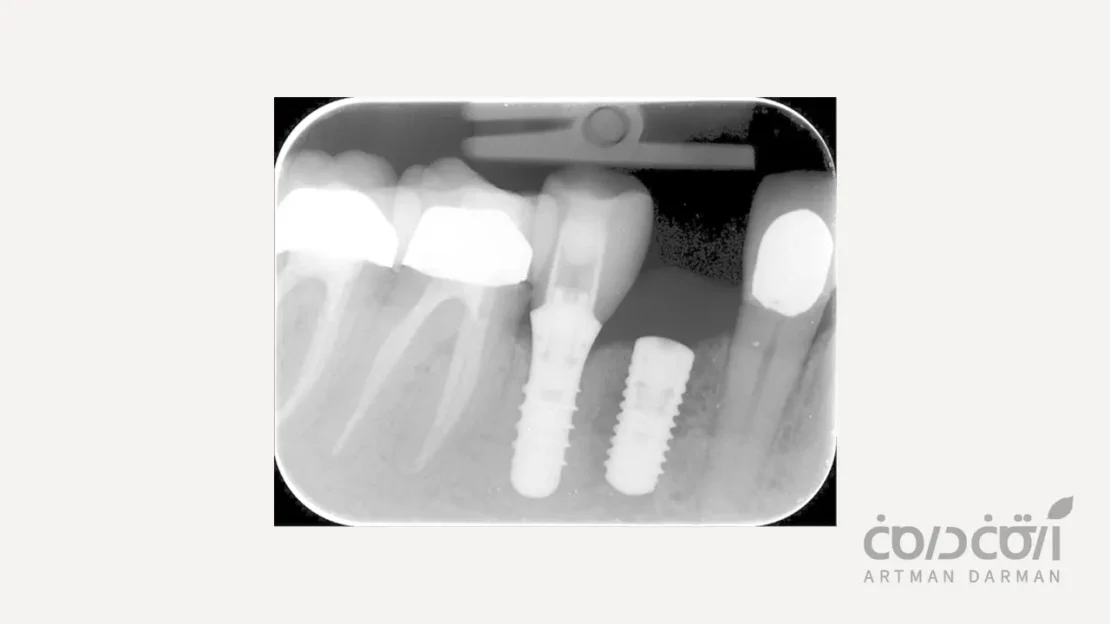

۲. شکست دیرهنگام (Late Failure) همراه با چالش های دوره نگهداری

این نوع شکست، ماه ها یا سال ها پس از اینکه ایمپلنت با موفقیت به استخوان جوش خورده و روکش روی آن قرار گرفتهاست، اتفاق می افتد. در این حالت، ایمپلنتی که قبلاً کاملاً سالم و پایدار بوده، به تدریج دچار مشکل می شود. دلایل افزایش احتمال شکست ایمپلنت دندان در درازمدت عبارتند از:

پری ایمپلنتایتیس (Peri-implantitis)

این، شایع ترین و مهم ترین علت شکست دیرهنگام است. پری ایمپلنتایتیس یک بیماری عفونی و التهابی است که در اثر تجمع پلاک باکتریایی در اطراف ایمپلنت ایجاد می شود. این فرآیند ابتدا لثه (مرحله موسوم به موکوزیت) را درگیر کرده و در صورت عدم درمان، به استخوان زیرین گسترش یافته و باعث تحلیل پیش رونده استخوان نگهدارنده ایمپلنت می شود. این تحلیل استخوان در نهایت منجر به لقی و از دست رفتن ایمپلنت می گردد.